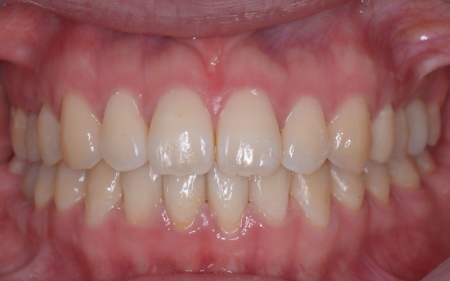

患者様は「健康な歯をできるだけ守りたい」との理由から、③のインプラント治療を希望されました。 まず、右上と左下の奥歯を抜歯しました。 矯正がある程度進んだ段階で、右上と左下のインプラント手術を実施しました。 インプラント手術後は矯正治療の仕上げを行い、装置を外しています。 治療終了後、下前歯の間に見られる三角形のすき間(ブラックトライアングル)が気になるとのご相談がありました。 |

| カウンセリング | 拝見したところ、右上と左下の奥歯に強い痛みが出ていました。 レントゲンで確認した結果、どちらも歯の根が割れていることが判明しました。 歯の根が割れたまま放置すると噛むときの痛みが続くだけでなく、炎症が広がって周囲の歯や骨にまで影響を及ぼすおそれがあります。 また、上下の歯を噛み合わせた際に前歯が噛み合わず隙間ができる開咬(かいこう)と呼ばれる噛み合わせも見られました。 以上のことから、抜歯後に歯を補う治療と噛み合わせを改善するための治療が必要と診断しました。 |